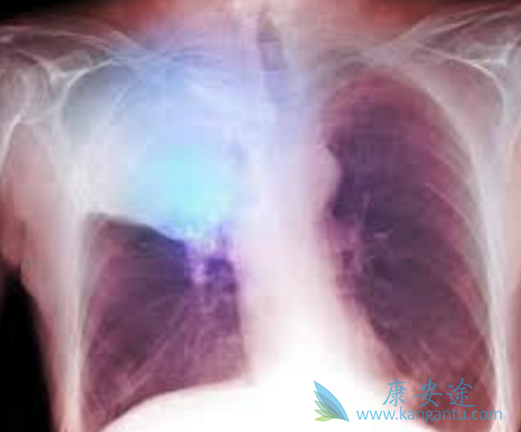

在两项Ⅲ期研究中,PD-1抗体纳武单抗(Opdivo)可以显着改善既往治疗过的晚期非小细胞肺癌的总生存。一项早前的对这类患者的I期研究的5年随访结果,并对5年幸存者的特征进行了总结。纳武单抗治疗使得一定比例的既往治疗过的晚期非小细胞肺癌患者持续缓解、长期生存。长期生存患者入组时情况各异、治疗过程中的特征差异很大。

患者与方法既往治疗过的晚期非小细胞肺癌患者,每2周接受一次1、3或10mg/kg的纳武单抗治疗,8周一疗程,长达96周。通过生存曲线Kaplan-Meier方法,估算自首次剂量起算的总生存。结果对于所有治疗患者(N=129),5年总生存率为16%。鳞状细胞(16%)和非鳞状细胞(15%)非小细胞肺癌患者的5年总生存率相似。16名5年生存者中,大部分(88%)为目前吸烟或以前吸烟,可以定量分析PD-1配体1(PD-L1)表达的5年生存患者中,70%的患者在入组时PD-L1表达≥1%。

按照实体瘤疗效评价标准1.0版评价,最佳缓解情况是,纳武单抗(Opdivo)治疗后12名5年生存者(75%)获得了部分缓解,2名病情稳定、2名疾病进展。9名5年生存患者(56%)完成了最高96个星期的纳武单抗治疗,4名(25%)由于不良反应中断治疗,3名(19%)由于疾病进展中断治疗。2016年11月数据库锁定时,12名5年生存患者以后未接受治疗,最后一次随访无疾病进展的证据。